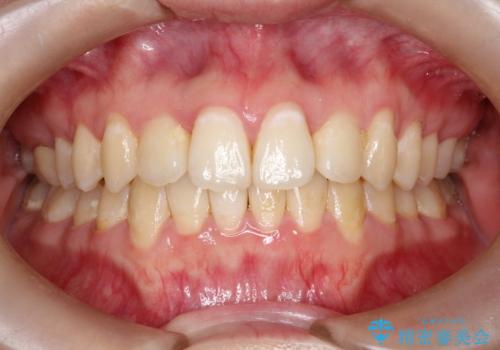

全体のガタガタをインビザラインできれいな歯並びへ